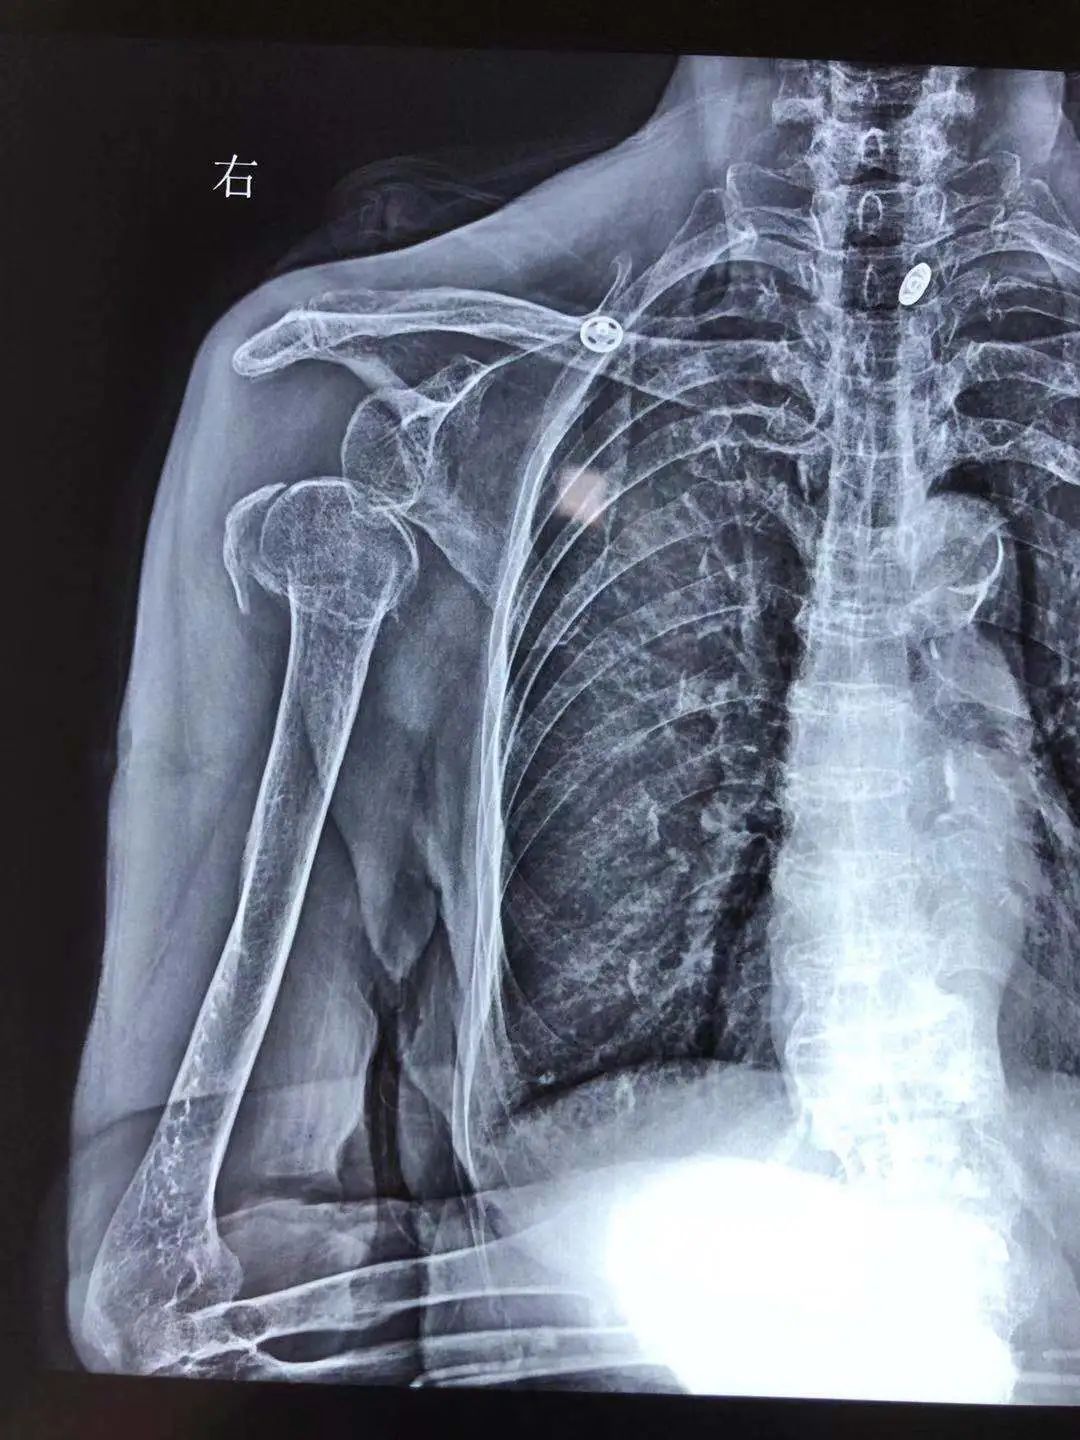

經(jīng)過(guò)拍片檢查,運(yùn)動(dòng)醫(yī)學(xué)科主任李堅(jiān)診斷黃奶奶為“右肩關(guān)節(jié)再次脫臼伴肱骨近端粉碎性骨折”,建議她做肩關(guān)節(jié)人工肱骨頭置換術(shù)。

李堅(jiān)主任立即制定了治療方案,并請(qǐng)康復(fù)醫(yī)院內(nèi)科、麻醉科、重癥監(jiān)護(hù)室等多學(xué)科專家會(huì)診和術(shù)前評(píng)估。11月2日,李堅(jiān)主任團(tuán)隊(duì)僅僅花了40分鐘,便順利為黃奶奶完成了“右側(cè)肩關(guān)節(jié)人工肱骨頭置換術(shù)”,刀口僅約7厘米。

術(shù)前

術(shù)后